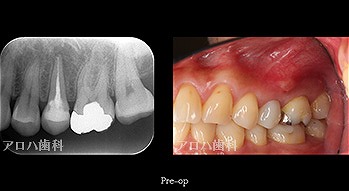

case9

自費の補綴

遠心口蓋側に限局性の深いポケット

上顎洞に波及している。